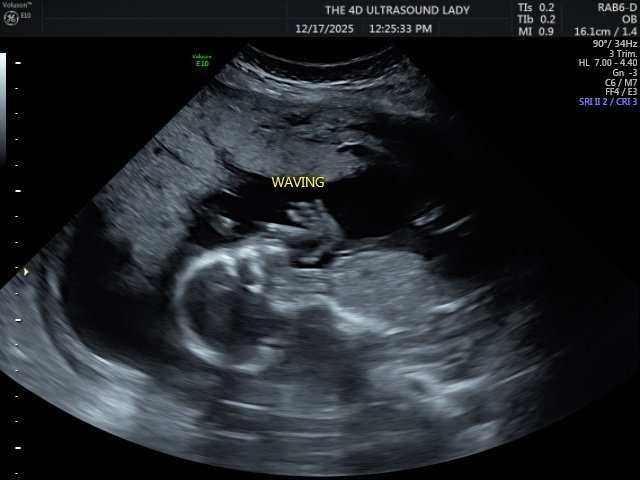

Right after the beach, we traveled to the States to spend Christmas in Alabama. This was the first time in a long while that we were able to truly slow down and rest, and it was very needed. We were exhausted, and that time ended up being incredibly refreshing. We were able to reconnect with our church family, spend lots of time with relatives, and see dear friends. We also found out during this trip that we are expecting another little girl in May, which has been such a joyful thing to celebrate.

- That our baby girl, Presley Kelly, continues to be healthy and that the pregnancy progresses smoothly

Jay, Kelsie, Logan, and Presley